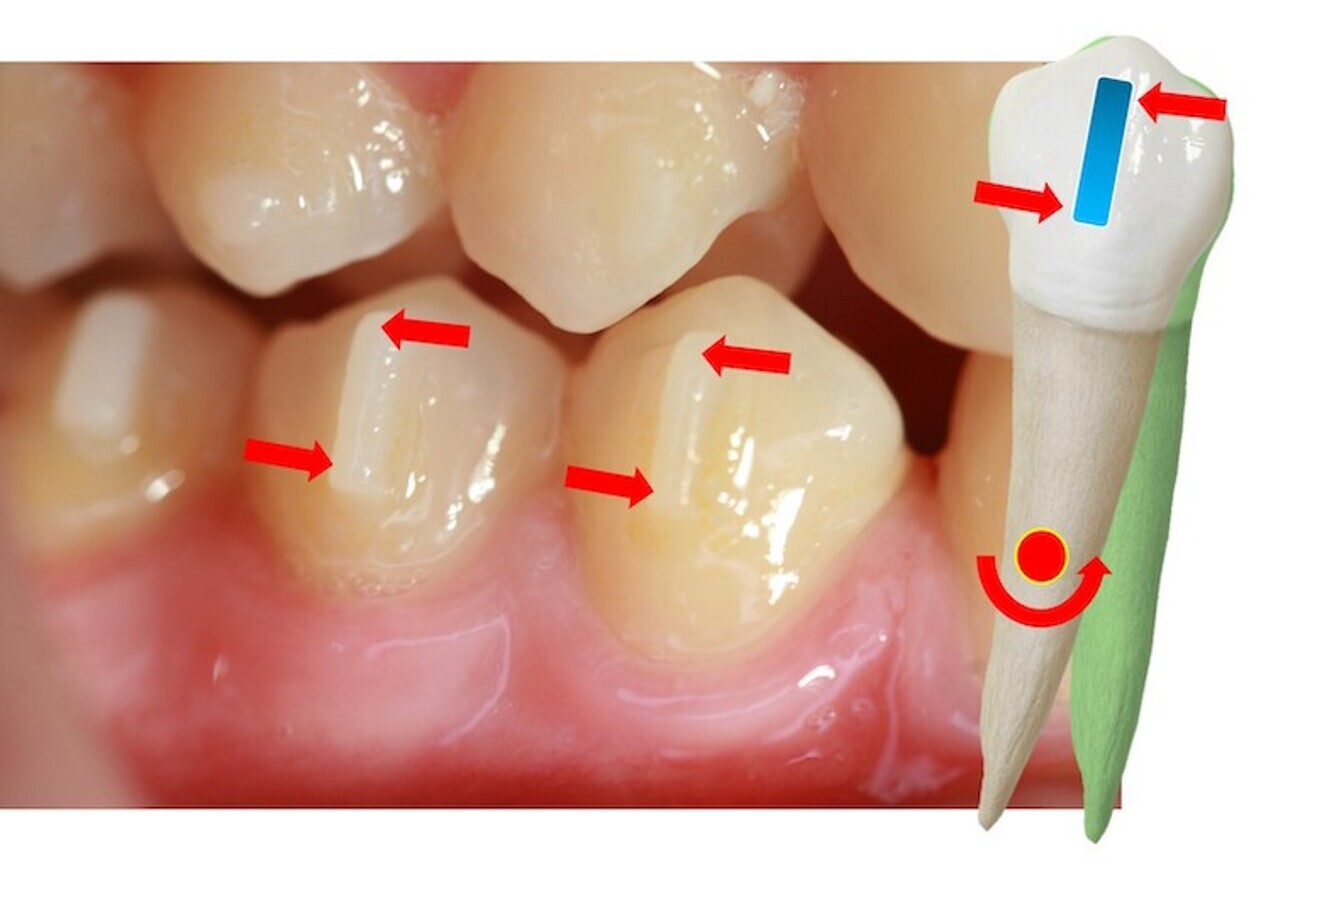

El movimiento de intrusión es otro ejemplo muy válido para comprender las diferencias biomecánicas entre utilizar brackets vestibulares, brackets linguales o alineadores (figura 2).

Figura 2. El movimiento de intrusión es un ejemplo de las diferencias biomecánicas entre utilizar brackets vestibulares, brackets linguales o alineadores.

La fuerza de intrusión que produce el arco en los brackets vestibulares pasa alejada del centro de resistencia del diente y esto genera un momento o inclinación vestibular del diente simultáneo al movimiento de intrusión. Si queremos evitar este momento o disminuirlo podemos actuar de dos maneras: dando torsión al diente con un arco rectangular que rellene la ranura o slot (par de fuerzas para generar torsión radicular negativa) o cinchando en distal el arco (control de la longitud de arcada). Cuando el bracket lo colocamos en lingual, su posición es cercana al eje mayor del diente y la fuerza de intrusión del arco pasa muy cerca del centro de resistencia radicular, disminuyendo el momento. Algo similar ocurre con los alineadores cuando añadimos en el plástico un punto de presión (PP) que redirija y concentre la fuerza de intrusión del plástico en la cara palatina del incisivo. Por tanto, la biomecánica a aplicar en uno u otro caso dependerá de nuestro plan de tratamiento y la necesidad, o no, de acompañar a nuestro movimiento de intrusión de un componente de inclinación vestibular. Debemos de realizar un movimiento combinado intrusión-inclinación en los típicos incisivos centrales lingualizados de la maloclusión de Clase II división 2ª y será más pura la intrusión, con mayor control de la torsión, en los centrales de la Clase II división 1º o en incisivos con una adecuada inclinación previa a la intrusión (figura 2).